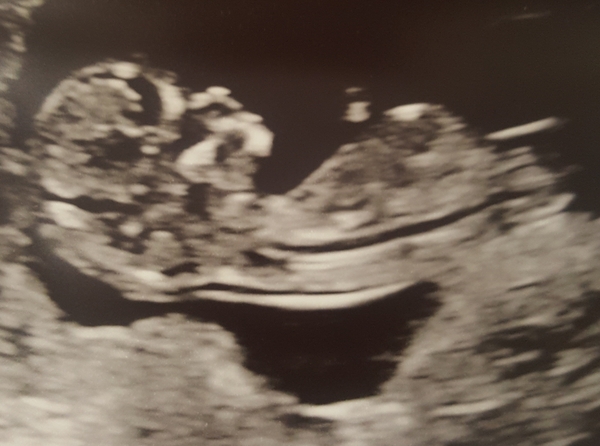

Had my 20 week scan today and we didn't find out the sex however wonder if anyone can tell from my scan pictures at 12 and 20 weeks the sex!

12 week vs 20 week scan

Girl. Your 20 week scan is so like my daughter's and I'm sure I can see the three lines for her life little lady parts!

Skull theory on the 20weeks would indicate girl :) x